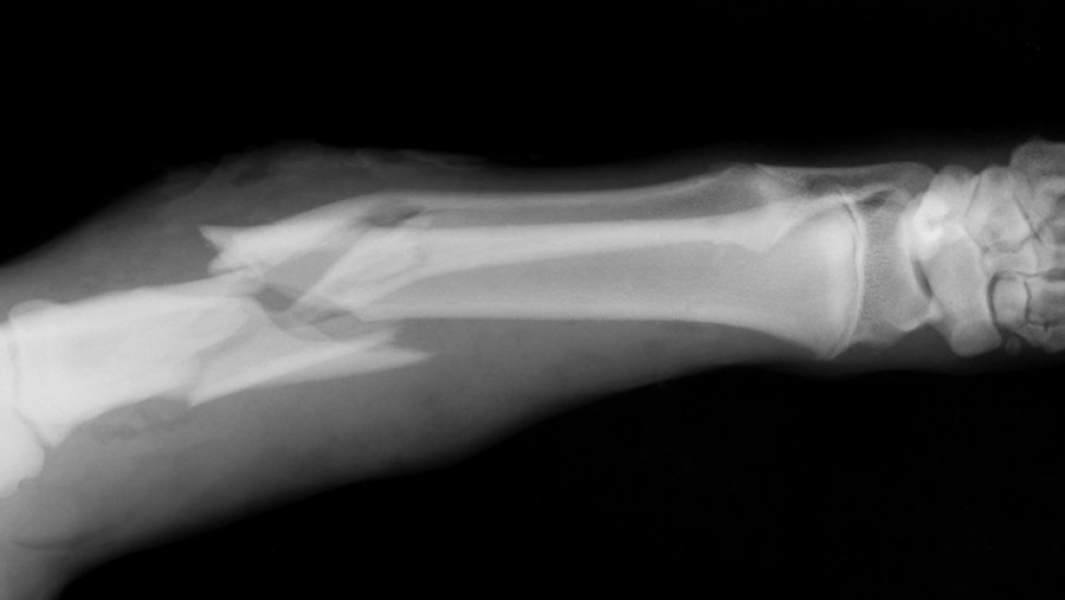

Рентгеновский снимок сломанной кости

Фото: Getty Images/Mark Kostich

Имплантаты из композитных материалов используются в регенеративной медицине в качестве клеточного каркаса при сложных травмах костной ткани. Композит, созданный учеными Курчатовского института, рассчитан на восстановление губчатых частей кости, которые располагаются по ее концам. В случае травмы поврежденная часть удаляется, а на ее место помещается композит. Применение материала позволяет организму продолжать функционировать так же, как и до повреждения.